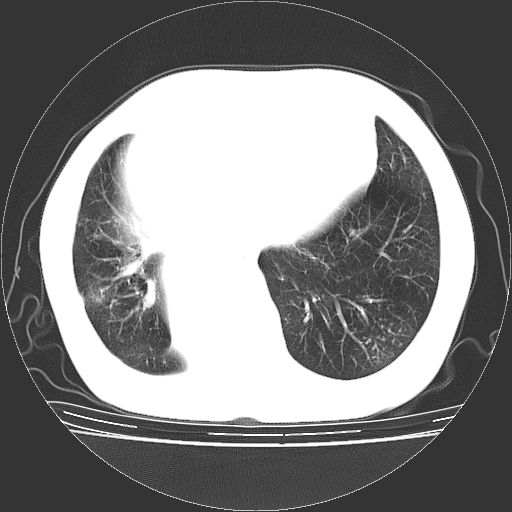

女,70岁,咳嗽、咳痰一个月,低热一周。

1.左上肺结核,部分纤维化。右肺中下叶部分肺不张,内见液化、坏死及点状钙化,右中下叶支气管壁增厚、管腔狭窄,见多个点状钙化,结合临床考虑支气管内膜结核,建议痰检查抗酸杆菌并参考血沉。两肺多个小圆点状高密度灶,境界模糊,多考虑结核肺内播散。但本人年龄较大首先应支气管镜检以除外右肺癌。